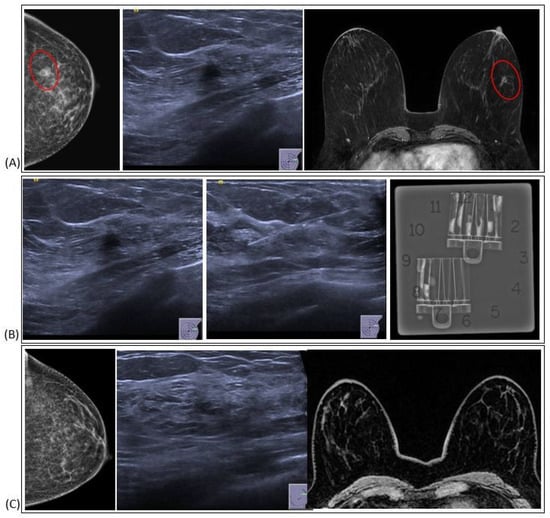

ADH is one of the most frequently recognized B3 lesions in breast pathology. It often correlates with grouped microcalcifications, nodules, or atypical densities visible on mammograms. Predominantly, ADH is detected in cases where calcifications appear on mammograms, constituting a significant majority (81.6%), while, in other studies, the prevalence of ADH detected alongside microcalcifications is even higher (86%) [7]. The MRI in these cases shows a lesion with nonspecific characteristics, such as a focal non-mass area or a small, irregular mass (Figure 1). Histologically, ADH is a small, low-grade, clonal intraductal lesion, that generally measures up to 2 mm in maximum diameter or consists of segments of a terminal ductal lobular unit.

Figure 1. ADH radiological features.

Figure 7. Vacuum-assisted excision (VAE): (A) Pre-procedural imaging. The red symbol highlight the position of the target lesion (B) VAE (C) Radiological assessment after bioptic procedure.